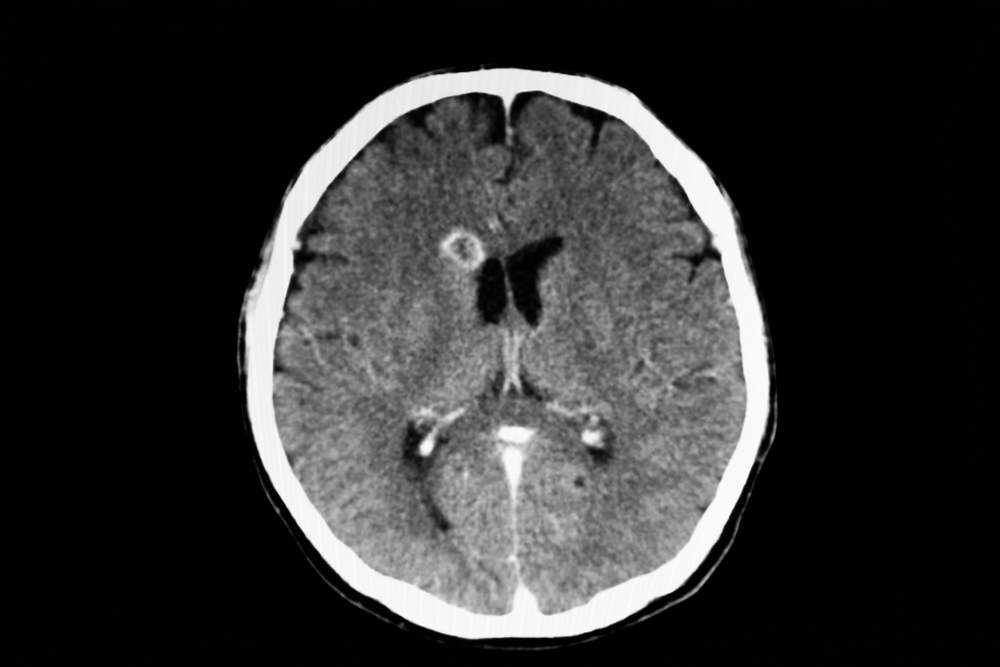

Huntington’s disease has long been one of the most devastating hereditary disorders known to science. Caused by a defective gene that produces a toxic protein, it leads to the gradual breakdown of nerve cells in the brain. Patients experience uncontrolled movements, cognitive decline, and severe psychiatric symptoms. Most tragically, there has never been a cure or even an effective treatment that could slow its relentless progression.

That has now changed. According to research published and reported by The Guardian and BBC News, the world’s first gene therapy targeting the root cause of Huntington’s has shown extraordinary results. The experimental treatment, known as AMT-130, uses a modified virus to deliver a healthy copy of the gene to brain cells, effectively silencing the faulty one.